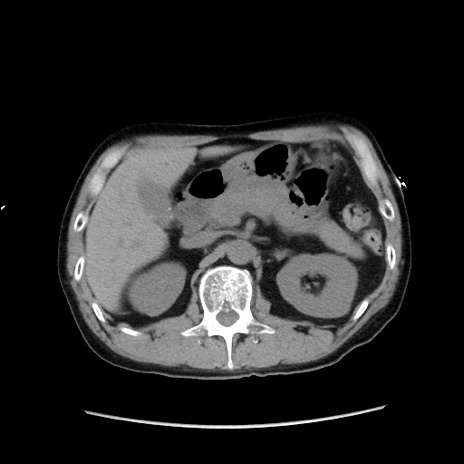

冠状断像

【症例】40歳代 男性

【主訴】腹痛

【現病歴】4時間ほど前に電車に乗車中に臍部上より腹痛出現。徐々に増悪し起立困難となり、救急外来受診。生ものは数日食べていない。今朝お雑煮を食べた。

【身体所見】BT 36.8℃、BP 117/84mmHg、HR 91/min、SpO2 97%、苦悶様、腹部:臍上部広範囲圧痛あり、反跳痛±

【データ】WBC 8100、CRP 0.03